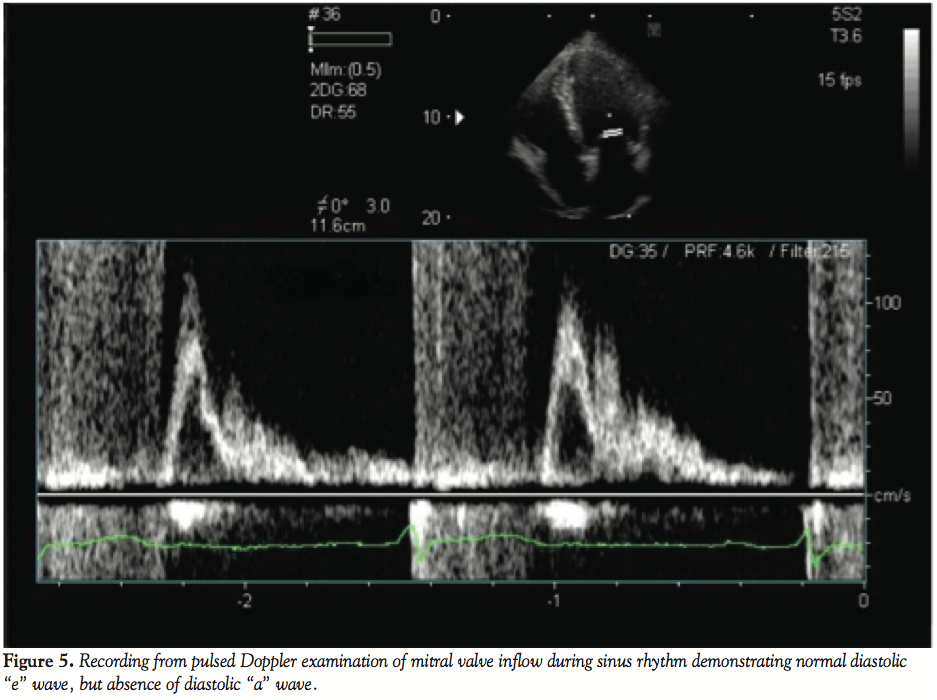

Presumably this finding was a result of the extensive ablation procedures the patient had undergone, creating interatrial conduction block, which resulted in the absence of electrical activity in the left atrium. This explained the presence of low amplitude atrial activity evident in the surface recordings despite the presence of sinus rhythm and then reverse typical atrial flutter, occurring in only the right atrial chamber. The 2 non-sinus rhythm ECGs were manifestations of atrial flutter with 2:1 AV conduction with and without bundle branch block with the flutter rate slowed by prior ablations and amiodarone therapy. Neither a sawtooth nor a sinusoidal ECG pattern was present, but careful scrutiny of lead II in both tracings did reveal low amplitude atrial activity compatible with this diagnosis. Radiofrequency ablation of the CTI resulted in bidirectional conduction block and restoration of sinus rhythm. Despite conversion, the left atrium recordings remained electrically silent (CS 3-4, CS 1-2) (Figure 4). The patient was discharged in stable condition and remained asymptomatic. Ultrasonography performed 3 months post-CTI ablation with pulsed Doppler examination of the mitral valve inflow demonstrated the absence of an “a” wave during diastolic filling despite continued maintenance of sinus rhythm compatible with atrial dissociation and absence of electromechanical activity in the left atrium. Anticoagulation therapy was continued indefinitely due to this finding.

The presented case was similar to these recent reports in that the patient had previously undergone extensive ablative and surgical procedures in an attempt to cure AF. Low amplitude P waves were present in the discharge ECG and then with the advent of the patient’s rhythm disturbance, atrial activity was not clearly apparent in the surface tracings. The electrophysiologic and echocardiographic data suggest that complete biatrial dissociation was present as a result of these procedures. Considering the anatomic relationships of the atria, the surface ECG in general reflects more left atrial activity than right and when the left atrium is electrically silent, ECG evidence of atrial activity is blunted. A subsequent invasive study documented the presence of CTI-dependent reverse typical atrial flutter localized only to the right atrium and this rhythm was treated with standard ablative approach. Intracardiac recordings reflecting left atrium remained electrically silent, which persisted late post-procedure, as no mechanical atrial function was evident 3 months post-procedure.

The potential for developing this phenomenon certainly must parallel the number of procedures and ablative lines that a patient undergoes in an attempt to improve AF. A resistant, highly symptomatic patient undergoing this number of AF procedures is somewhat atypical in our experience, but considering that AF ablation is somewhat imperfect in terms of outcomes in its present practice, increasing numbers of patients undergoing multiple procedures can be anticipated. Considering this, postablation patients, particularly those who have undergone multiple, extensive procedures, should be monitored for the occurrence of unusual rhythms and consideration given to the diagnosis of atrial dissociation when low-amplitude atrial activity is identified on the surface ECG. Diagnosis may be difficult without invasive electrophysiologic study although ultrasonography may reveal clues in suspicious patients by demonstrating evidence of electromechanical dissociation.10 Similarly, improvement in these echo-Doppler abnormalities may signal resolution of the dissociated rhythms and improved atrial electrical conduction.

Absence of mechanical left atrial function was previously described in patients post-conversion from AF, and in many patients, these stunned atria exhibit gradual recovery of functional activity over time.11 Mantana et al described echocardiographically normal right atrial mechanical function and absent left atrial function 7 months post-conversion to sinus rhythm.12 However, some of these cases may be dissimilar to ours in that electrical activity may be present but the atrial musculature cannot be stimulated resulting in absent atrial mechanical function. The mechanism of mechanical dysfunction in the presented case is unique in that left atrial electrical activity is presumably inhibited by extensive areas of atrial conduction block that were created by the ablative processes.